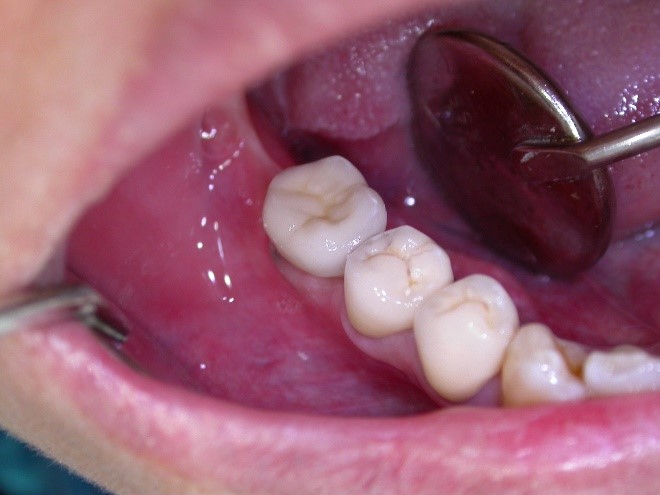

Implantát v postranním úseku chrupu.